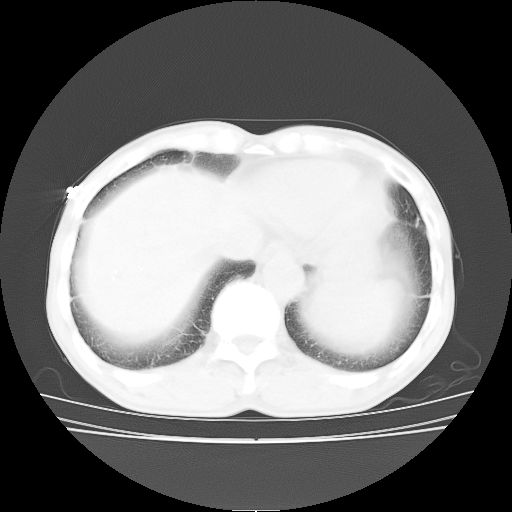

标题: CT25795:感冒后反复咳嗽两月余,痰中带血半月余。X诊断“肺 [打印本页]

标题: CT25795:感冒后反复咳嗽两月余,痰中带血半月余。X诊断“肺

1.双肺肺梗塞(理由:病灶呈三角形,与胸膜相连且局部胸膜肥厚,左心室增大)伴肺感染。

考虑两肺感染性病变,左肺上叶舌段肿瘤性病变待排;建议抗炎治疗后复查。